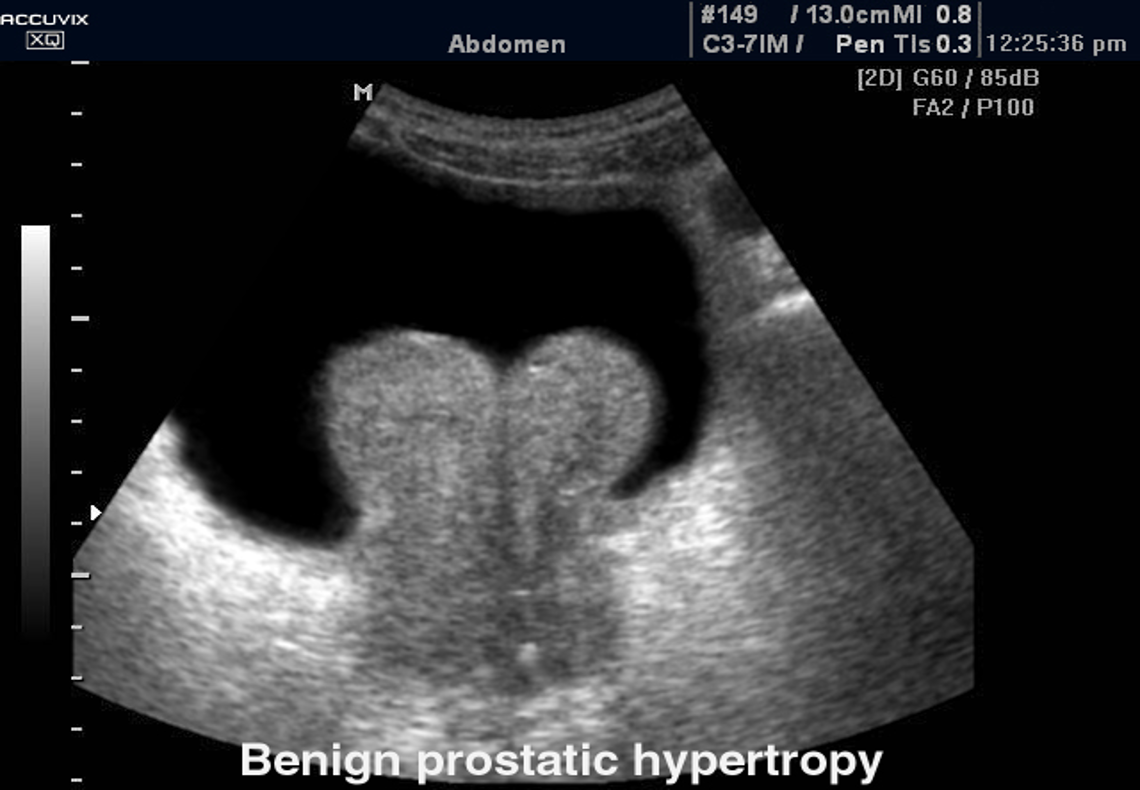

Ultrasound : Transabdominal ultrasound (TAUS)

Indications: Ultrasound pelvis: Consider prior to initiating treatment to assess the size of the prostate.

Supportive findings of BPH:

- Increased total prostate volume

- Elevated PVR volume

- Evidence of bladder outlet obstruction (e.g., bladder wall thickening and hydronephrosis ).

Case . 75 years old male with retention of urine